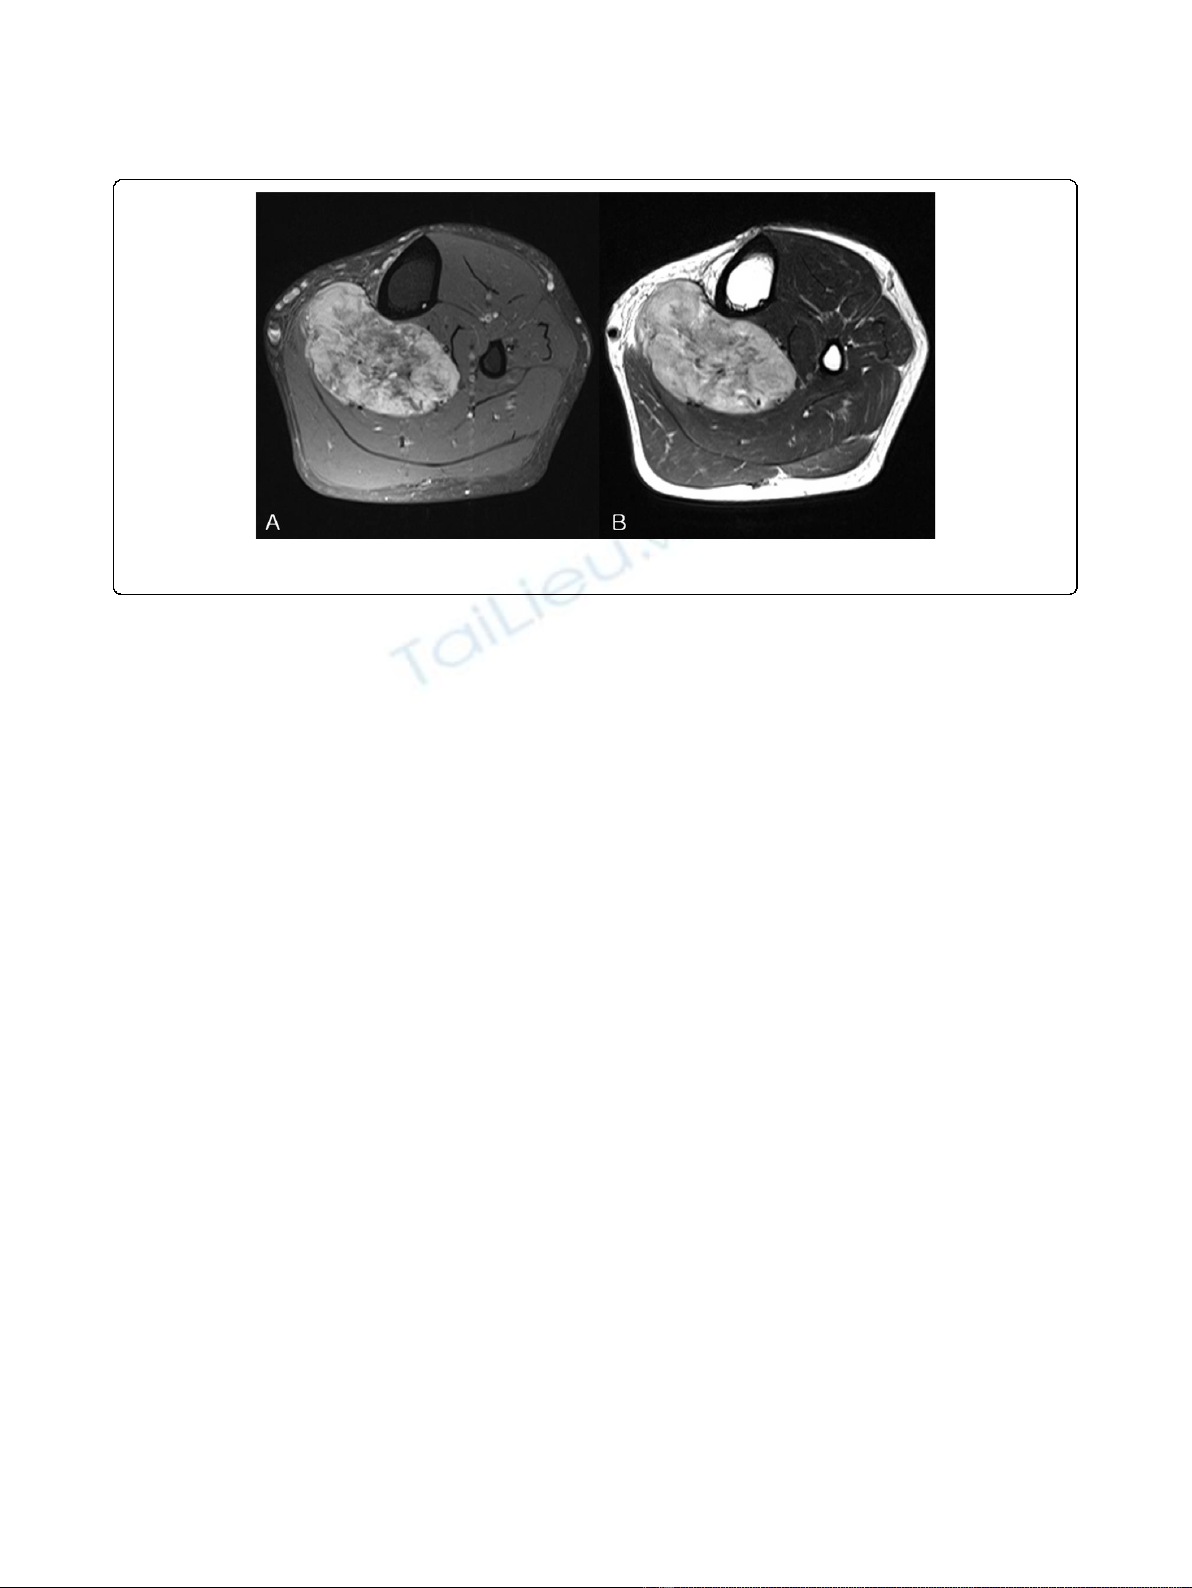

plain radiographs. In all three cases of alveolar soft part

sarcoma, the characteristic MRI finding was of high

signal intensity with signal voiding on T1 and T2 images

(Figure 2), which was attributed to the presence of abun-

dant blood vessels. However, no other tumor-specific

other soft tissue sarcomas, alveolar soft part sarcomas

have characteristic radiologic features, that is, MRI T1-

and T2-weighted images have high signal intensities and

signal voids due to the presence of abundant blood ves-

sels [12-14]. Accordingly, these tumors can be misdiag-

nosed as hemangiomas or A-V malformations. In the

Figure 2 MRI images of an alveolar soft part sarcoma. (A) An axial T1-weighted fat-suppressed image and (B) an axial T2-weighted image.

High signal on T1FS, T2WI with multiple signal voids are apparent.